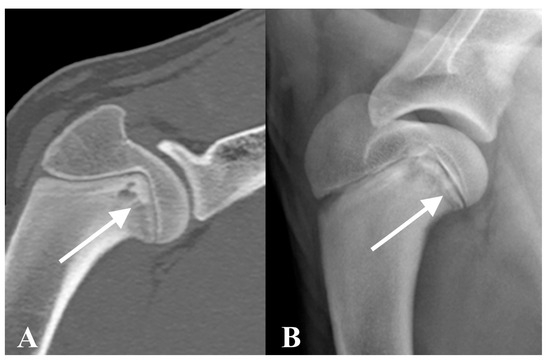

A full-body CT study was performed before and after intravenous administration of iodinated non-ionic contrast medium. CT findings revealed bilateral, symmetrical metaphyseal changes affecting the proximal humerus, distal radius and ulna, proximal and distal femur, proximal and distal tibia and fibula, and distal metacarpal and metatarsal bones. These changes included an irregular, thin hypoattenuating metaphyseal band of lysis parallel to the physis, associated to a zone of metaphyseal increased attenuation consistent with bone sclerosis (Figure 1 and Figure 2A). The bones were affected to different degrees, some of the changes were very subtle, and the distal ulnae were most severely affected. Very mild new bone formation was incompletely encircling several metaphyses, likely representing normal cutback zones or early paracortical cuffs. No abnormalities were observed within the joints or subchondral bone, and no abnormal contrast enhancement was detected. Mild generalised lymphadenomegaly was present, which was considered a normal age-related finding, or mild reactive hyperplasia. Mild bilateral hypoattenuating foci were present, affecting both mandibular condyles with very mild irregularity of the subchondral bone. The overall imaging findings were suggestive of MO.

Radiographs of the left humerus and bilateral carpi and tarsi revealed an irregular, radiolucent metaphyseal line parallel to the physis within the proximal humerus, and distal radius, ulna, and tibia bilaterally, creating a “double physis sign” (Figure 2B). Mild-to-moderate sclerosis was present adjacent to the radiolucent metaphyseal lines. New bone formation separated from the cortex was present around the affected metaphyses of the radius, ulna, and tibia, consistent with metaphyseal paracortical cuffing, and moderate soft tissue swelling centred on the metaphyses was also noted (Figure 2B).

This study describes the imaging findings of four dogs with presumed diagnosis of MO based on CT images. In all cases, bilateral, irregular, hypoattenuating metaphyseal bands of lysis were observed, running parallel to the physis. These lesions were symmetric, often bordered by areas of metaphyseal sclerosis, and commonly associated with mild periosteal new bone formation. Despite the consistent nature of these imaging features, the severity of the lesions varied both within individual patients and across the different cases. Subtle changes, such as those shown in Figure 1, may represent early manifestations of MO and are unlikely to be detectable on plain radiographs.

Figure 1. Case 1. Transverse CT image of the proximal humeri with bone algorithm reconstruction at initial presentation. Bilateral symmetric thin hypoattenuating metaphyseal band is present parallel to the physis (white arrow).

Figure 2. Case 1. Sagittal Multiplanar Reconstruction (MPR) image with bone algorithm of the distal antebrachium on CT at presentation (A) and mediolateral radiographic view of the distal antebrachium one month after presentation (B). A thin irregular hypoattenuating metaphyseal band is present in the distal radius and ulna, the changes are more severe in the ulna at presentation and mild in the radius (A). In the radiograph (B), the radiolucent band is associated with adjacent bone sclerosis and mild new bone formation is present cranial to the radius and caudal to the ulna, suspected to represent paracortical cuff (white arrow). Moderate soft tissue swelling centred at the metaphyseal region can also be noted in (B).